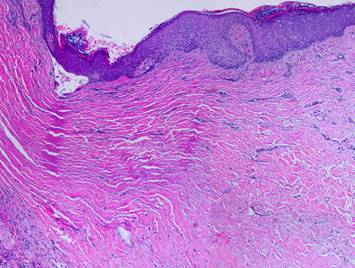

The second maturation process is the restoration of a normal epithelium.  Epithelium arrives on the wound surface in two ways – naturally by migration from wound margins or else by surgery (skin grafts).  Either way, the young closed wound typically has but a thin epithelium (epidermis in these examples).  After epithelial cells arrive, they reestablish a basal stratum germinativum.  As they resume their normal functions of keratinization and epithelial cell replenishment, maturation events can be seen.  Acanthocyte proliferation thickens the epidermis and leads to the formation of rete pegs as vascular tufts tile the subepithelium to maintain blood supply to the thickened lamina.  The metabolically active epidermis requires logistical support, so a lamina propria develops, the papillary dermis.  The deeper reticular dermis is a primary structure formed embryologically or in a regenerative biomatrix.  The papillary dermis is a secondary structure, engineered by the epidermis, which does not appear until epidermis has covered the wound.  The two dermal strata have distinctly different origins, purposes, and morphologies.

Right upper, young epidermis soon after a skin graft.  The epidermis is thin, the stratum germinativum is still immature, there is no papillation, and no specific or differentiated histo-morphology of the subjacent scar.  Right middle, a mature regenerated epidermis.  Normal acanthosis with rete ridges and mild superficial papillomatosis is present.  Blood vessels are present in each dermal papilla – these are the vascular tufts which supply the epidermis.  The dermal layer has two distinct tangential zones.  The upper layer is the papillary dermis, triggered by the overlying epidermis when it was placed on the underlying reticular layer.  The new papillary dermis is fairly normal in appearance - it may improve further with age, but it already looks like normal native papillary dermis.  The bottom reticular layer is NOT at all like normal reticular dermis.  It is the scar from the previous open wound.  It is cellular and has lamellated collagen which is dense and non-compliant, but with relatively thin collagen bundles compared to normal reticular dermis - i.e. it is scar.  Right lower, as epidermis matures, other normal features appear, such as Langerhans cells and, depending on the source of the new epithelium, melanocytes and melanin.  These are all innate features of the epidermis and epidermal-dermal interactions, and they occur independent of what had previously happened in the mesenchymal dermis or scar or wound module underneath.  Left, two panes showing maturation of epithelium after an ankle ulcer.  Left is a recently healed skin graft showing fragility, brittleness, accelerated desquamation, and inconsistency of the corneum.  Right is a view a year later when epidermis has returned to normality.  This maturation corresponds to the changes seen in the histology views.